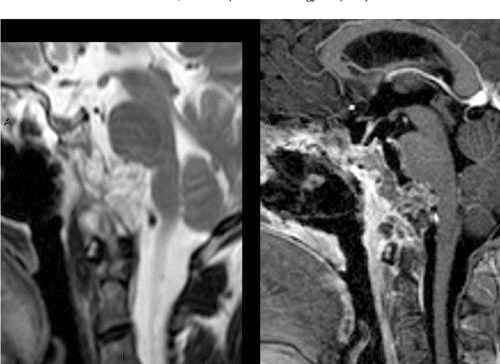

En anatomía humana, recibe el nombre de clivus una formación ósea situada en la base del cráneo. Está formado por la unión del cuerpo del hueso esfenoides con la porción media del hueso occipital. Puede observarse con claridad en la cara interna de la base del cráneo, limita por delante con la silla turca, por detrás con el agujero magno y en la región derecha e izquierda con los dos peñascos de los huesos temporales. Puede dividirse en tres sectores, el clivus superior, más cercano a la silla turca, el clivus medio y el clivus inferior próximo al agujero magno. Infrecuentemente se desarrollan tumores óseos malignos en el área del clivus, entre ellos el cordoma de clivus y el condrosarcoma de clivus.[1] [2][3]

El esfenoides comunica el cerebro con las órbitas, cara y cuello suprahioideo. Forma la parte superior del clivus, las alas mayores, las alas menores y los procesos pterigoideos. El clivus es la parte de la base del cráneo que conecta el dorso selar y foramen mágnum. Está formado por parte del cuerpo del esfenoides y el basioccipucio. Inferiormente esta limitado por el nasofarinx.[3]

El clivus es un punto de referencia importante para verificar la alineación anatómica atlantooccipital; el clivus, cuando se ve en una radiografía lateral de la columna C, forma una línea que, si se extiende, se conoce como línea del clivus de Wackenheim. La línea del clivus de Wackenheim debe pasar a través de las guaridas del eje o ser tangencial a él.[4]